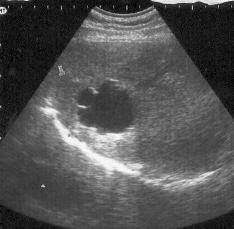

Descripción de las Imágenes

:Riñón derecho de forma y tamaño normal. Relación corticomedular y sinusal conservada. Diámetro long. 6,7 cm. Anteroposterior: 4,2 cm

En proyección renal izquierda se evidencia dos formaciones anecoicas de contornos definidos refuerzo posterior de 4,4 cm y 3,0 cm. Sin imagen de cortical renal.

Diagnóstico

:Riñón displásico multiquístico